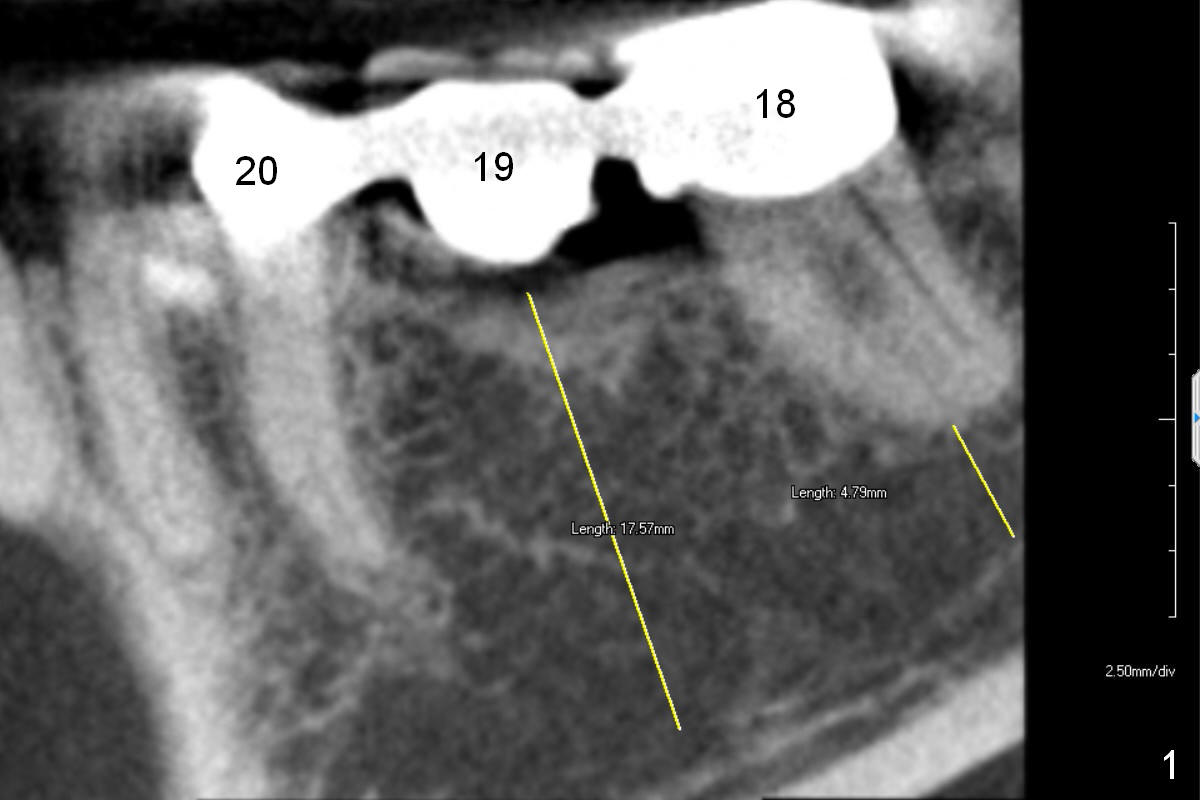

A 68-year-old lady has had a lower right bridge for 10 years (Fig.1,2 (CBCT section), Fig.3 (3 D image)). There is caries underneath #20 retainer (mesiolingual) with symptom. The retainer and the pontic at #19 will be removed. The tooth #20 may need root canal therapy. An implant will be placed at #19, but the crest is narrow (Fig.2 coronal section).

Because of pain, the bridge has been removed partially. Caries in the tooth #20 (Fig.7 *) is confirmed; root canal therapy has been done. With bone expansion, the bone level implant can be placed at the crest. That is, it can be longer (Fig.7: 13.5 mm) than the one placed subcrestally (Fig.2: 10 mm).